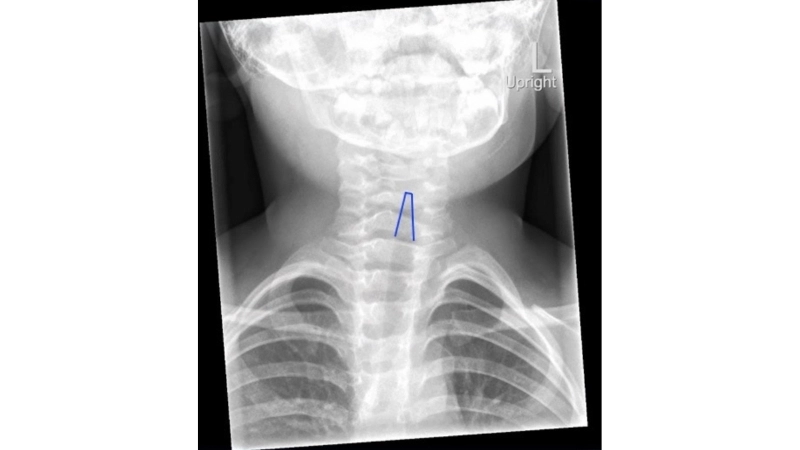

Croup visual guide with adenovirus rash cases

Image description of Croup

Croup is a respiratory condition most commonly affecting young children, caused by viral infections that inflame the upper airway. Symptoms include a barking cough, stridor, and hoarseness. Prevention focuses on hygiene, avoiding irritants, and vaccinations.